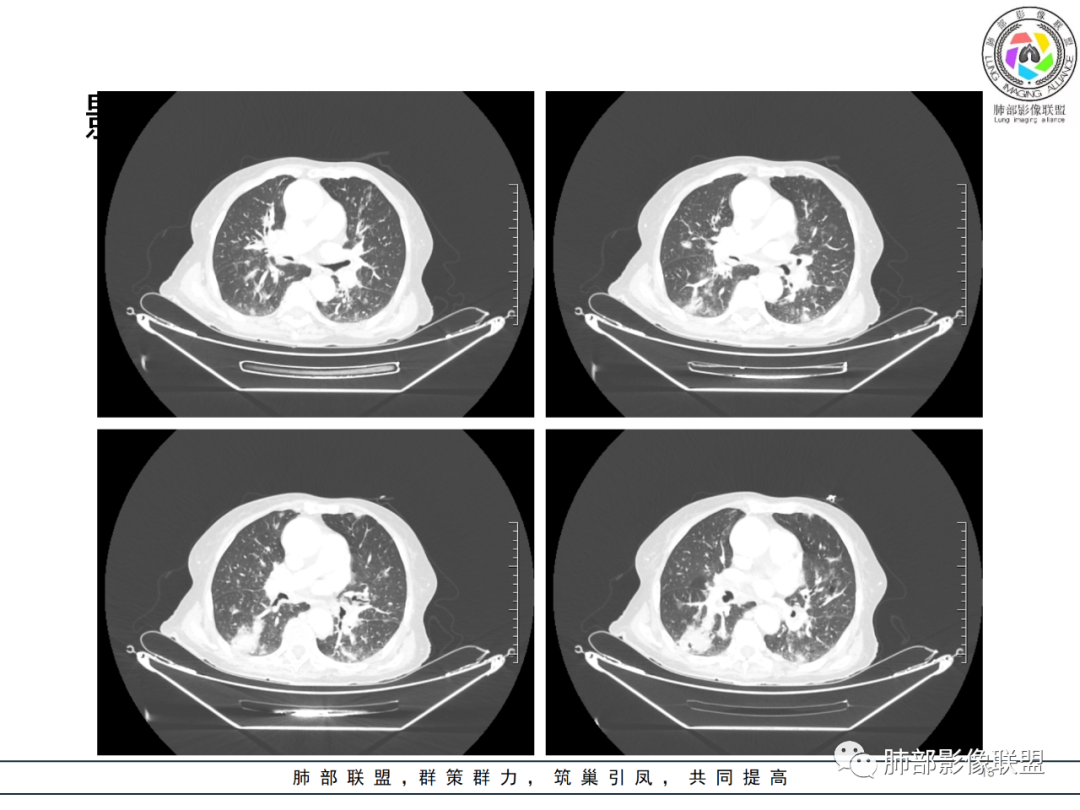

影像资料

老年女性 3个月前发热,双肺支气管血管束增粗改变。3个月后再次发热,影像见双肺广泛支气管血管束明显增粗,较前进展,并延续进入纵隔,另外增强见双肾周增多软组织密度,左肾明显且肾门处形成肿块样改变。综合考虑肿瘤性病变可能性大,1.小圆细胞肿瘤类病变,淋巴瘤?2 全身组织细胞类病变,如ECD,需要看看骨组织有无问题。3 左肾恶性肿瘤并淋巴道播散,如弥漫性尿路上皮癌。最后考虑 淋巴瘤>ECD>左肾恶性肿瘤并转移。

82岁女性,反复发热入院,查外周血白细胞升高,抗生素治疗可缓解,支持细菌感染性发热,结合肾脏肿瘤,考虑泌尿系感染发热;CT提示双肺多发毛玻璃影,右下肺多发大结节影,3月复查,双上肺毛玻璃影/混合毛玻璃影增多,部分呈点晕征,右下肺多发肿块,可见支气管穿行,双下肺中轴间质增厚,左肾占位,肺部病变考虑:1.淋巴瘤 2.肾癌肺转移

如果说两肺病变生就一张“大众脸”,但腹部异常影像却带给我们一些重要线索! 双肾病变变现为浸润性累及肾周、延及深静脉,而非典型膨胀性,低密度少血供,腹膜后肿大的淋巴结同样强化不明显,这些都符合典型的浸润性肾淋巴瘤的影像表现。注意患者肾上腺低密度结节影及脾脏多发结节影,脾脏恶性肿瘤尤以淋巴瘤最为常见!

结合肺部的分析,临床LDH升高等,我们有理由怀疑其全身系统性疾病—“淋巴瘤”。

淋巴瘤从原发到继发肺浸润,不光可以是表现为典型的大片实变、肿块、结节,还可表现为肺间质的弥漫性浸润、或者散在的斑片影、粟粒样的改变,到单纯围绕中轴间质的增生性改变等等,可以说是变化莫测、扑朔迷离,这给我们的诊断带来很多的困惑和迷茫,但是从点到面再从全身回到肺部,间接的临床影像信息也会给我们带来决定性意义的证据!